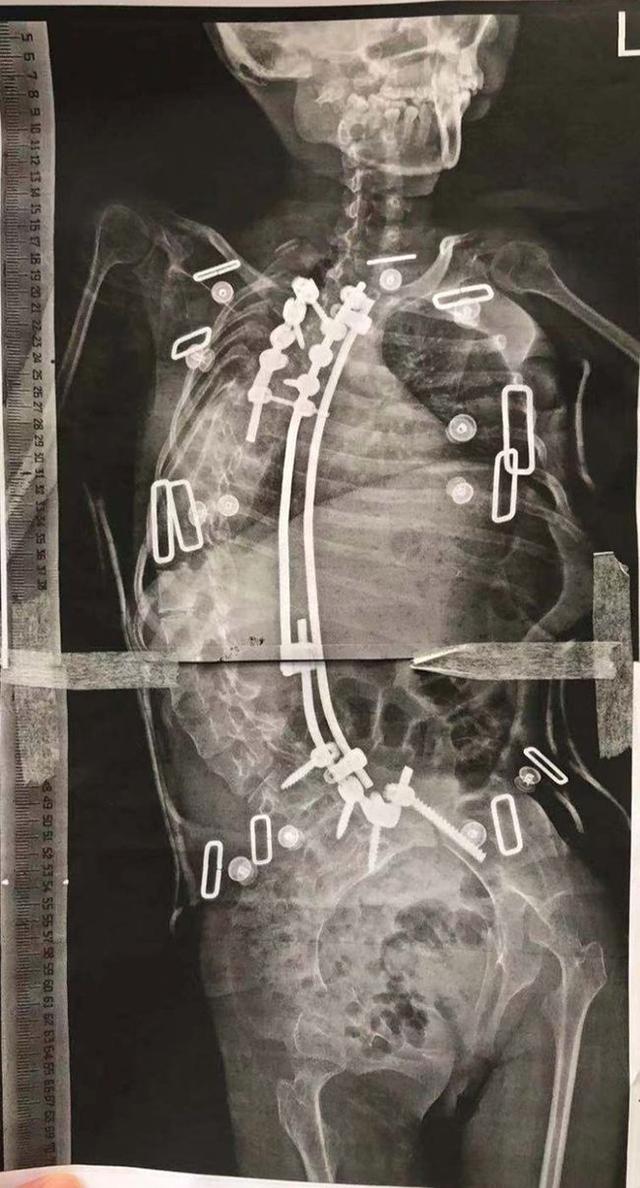

患儿术前全脊柱影像图

术后X光显示,侧弯角度减小至82度,矫形率达到53%。

术后全脊柱影像图